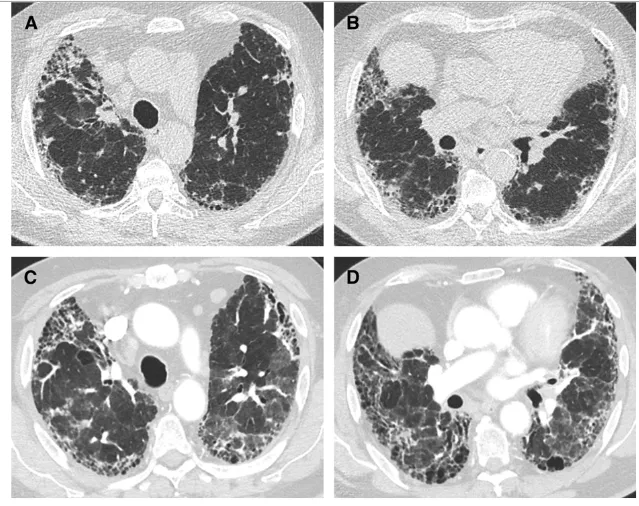

Acute Exacerbations of Interstitial Lung Disease: Evolving Perspectives on Diagnosis and Management

Interstitial lung diseases (ILDs) are a heterogeneous group of chronic lung diseases caused by several potential etiologies but for many, the cause of a given ILD remains unknown. Accurate epidemiologic data are hard to find because of varying definitions, overlapping characteristics once thought to be unique to specific diseases, and ongoing changes in how ILDs are diagnosed and managed. In addition, there are significant variations in prevalence among different geographic populations, likely reflecting a combination of genetic and environmental differences. Certain risk factors, including exposure to cigarette smoke or environmental toxicants (asbestos, silica, fracking, coal dust, and air pollution), genetic mutations, and single nucleotide polymorphisms, have all been associated with developing interstitial lung disease. Due to the availability of high-resolution computed tomography (CT) scans, earlier and broader recognition of subtle imaging changes, and an aging worldwide population, the incidence and prevalence of ILDs are increasing. While a given cause of particular interstitial lung disease may vary, patients often experience breathlessness and a non-productive cough due to impaired alveolar gas exchange. Patients with ILD are prone to the development of acute exacerbations, marked by acute or chronic respiratory failure because of an acute exacerbation of the underlying lung disease. In this review, we discuss the definition of an acute exacerbation and comment on what is known about the underlying pathophysiology in exacerbations of idiopathic pulmonary fibrosis and other ILDs. We also emphasize the similarities in the clinical presentation of the acute exacerbations regardless of the underlying ILD, highlight key prognostic features of the diagnosis, and underscore the importance of interdisciplinary management of acute interstitial lung disease exacerbations.

Keywords: Idiopathic Pulmonary Fibrosis (IPF); Interstitial Lung Disease (ILD); Acute exacerbation of ILD (AE ILD); Corticosteroids; Mechanical ventilation; Extracorporeal membrane oxygenation (ECMO)